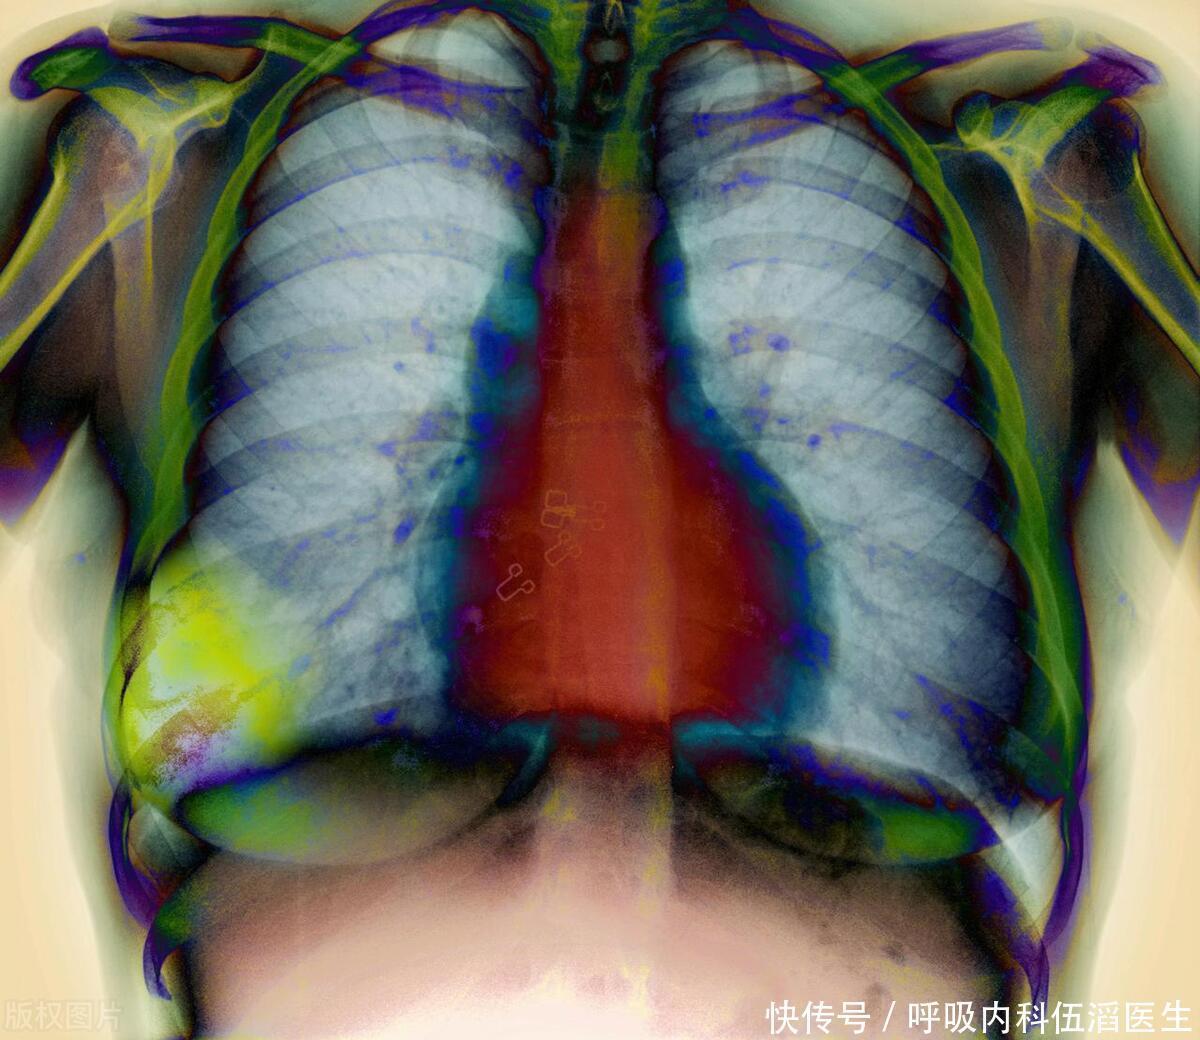

头部若出现 4 种异常,可能是肺癌的信号,该做一下检查了

肺癌

肺部

胸腔积液